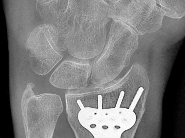

A 28-year-old sustains a laceration to the volar aspect of the digit in Zone II, requiring surgical exploration and flexor tendon repair. To prevent tendon bowstringing and maximize biomechanical excursion efficiency, which two annular pulleys are the most critical to preserve or reconstruct?

The flexor tendon sheath mechanism comprises five annular (A1-A5) and three cruciform (C1-C3) pulleys. The A2 and A4 pulleys are the major pulleys responsible for preventing bowstringing of the flexor tendons. The A2 pulley arises from the proximal phalanx, and the A4 arises from the middle phalanx. Biomechanical studies have shown that preserving or reconstructing A2 and A4 is critical to maintaining normal digital kinematics and work of flexion.